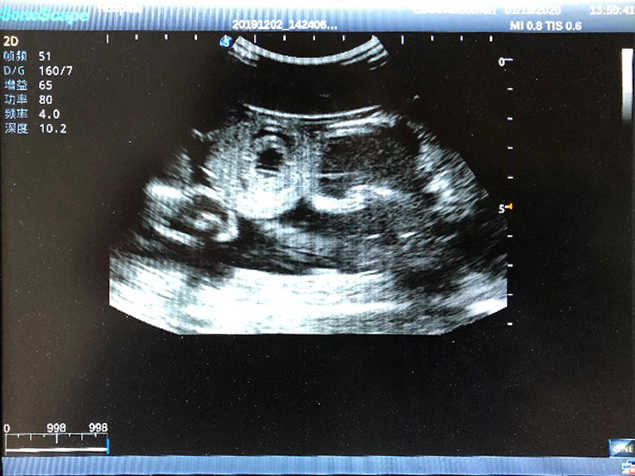

Abdominal Ultrasound Phantom

Model TYE1569

Outline

This product is a true-to-life male torso designed for abdominal ultrasound training. It offers you an effective solution for preparing learners for routine abdomen checkup including percussion, various puncture under ultrasound guidance and ultrasound image reading. The realism of the product and the skillset specific to abdominal examination techniques will bring learners competence and confidence.

Skills Gained

· Familiarity with the abdominal regions and underlying anatomy

· Recognition of abdominal vessels & organs using ultrasound

· Recognition of various abdominal pathologies using ultrasound

· Handling ultrasound transducers

· Practice in abdominal palpation, percussion & various centeses

· Through ultrasound, identification of safe needle/catheter insertion sites

Features

· Realism:

Soft material with realistic touch and feel

· Anatomy:

Correct anatomical structures and obvious landmarks, including superior iliac spine, navel, pubic symphysis and groin etc.

· Key Features:

1)  Ideal for trainings like ultrasound-guided abdominocentesis with visible ascites flowing out, ultrasound-guided femoral artery & venous puncture

2)  High quality ultrasound image with clear structures like gallbladder, liver, intestines, arteries and veins etc.

3)  Compatible with all types of clinical ultrasound machines

4)  ltrasound gallbladder pathologies like cholecystitis, gallstone and polypoid degeneration

5)  Normal & pathological ultrasound live and intestine models inside

6Durable for repeated use & easy replacement for consumable parts